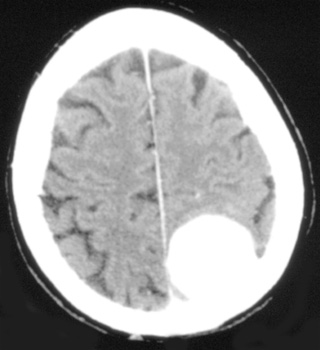

Head CT > Tumor > Meningioma

Meningioma

Meningiomas are the most common extra-axial neoplasm of the brain. Middle-aged women are most frequently affected. Twenty percent of meningiomas calcify. On CT, meningiomas are usually isointense to gray matter.

![]() Bone windows confirm calcification within the mass. ![]() Axial, post contrast CT demonstrating broad based enhancing extra-axial mass. |